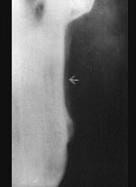

边缘性骨髓炎好发于 ( )

A.上颌骨体部B.下颌升支C.上、下颌牙槽骨D.下颌骨体部E.上颌结节

B